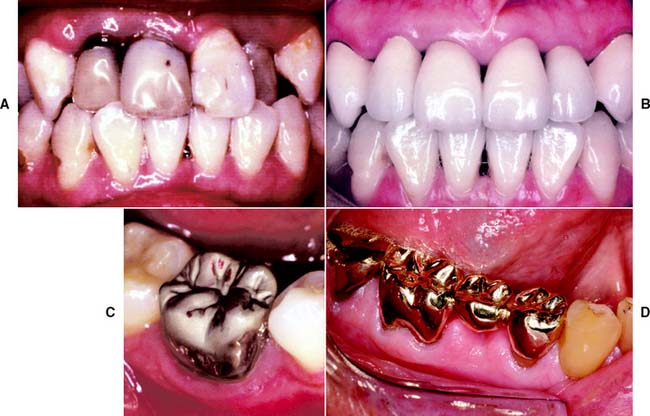

Fixed prosthodontic treatment involves the replacement and restoration of teeth by artificial substitutes that are not readily removable from the mouth. Its focus is to restore function, esthetics, and comfort. Fixed prosthodontics can offer exceptional satisfaction for both patient and dentist. It can transform an unhealthy, unattractive dentition with poor function into a comfortable, healthy occlusion capable of years of further service and greatly enhance esthetics (Fig. 1-1A and B). Treatment can range from the fairly straightforward restoration of a single tooth with a cast crown (Fig. 1-1C) or replacement of one or more missing teeth with a fixed dental prosthesis (Fig. 1-1D) or implant-supported restoration to a highly complex restoration involving all the teeth in an entire arch or the entire dentition.

Fig. 1-1 A severely damaged maxillary dentition (A) restored with metal-ceramic fixed prostheses (B). C, Complete cast crown restores mandibular molar. D, Three-unit fixed dental prosthesis replacing missing mandibular premolar.

(C, Courtesy of Dr. X Lepe. D, Courtesy of Dr. J. Nelson.)